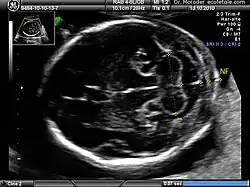

A nuchal scan or nuchal translucency (NT) scan/procedure is a sonographic prenatal screening scan (ultrasound) to detect chromosomal abnormalities in a fetus, though altered extracellular matrix composition and limited lymphatic drainage can also be detected.[1]

Procedure

Nuchal scan (NT procedure) is performed between 11 and 14 weeks of gestation, because the accuracy is best in this period. The scan is obtained with the fetus in sagittal section and a neutral position of the fetal head (neither hyperflexed nor extended, either of which can influence the nuchal translucency thickness). The fetal image is enlarged to fill 75% of the screen, and the maximum thickness is measured, from leading edge to leading edge. It is important to distinguish the nuchal lucency from the underlying amniotic membrane.[9]

Normal thickness depends on the crown-rump length (CRL) of the fetus. Among those fetuses whose nuchal translucency exceeds the normal values, there is a relatively high risk of significant abnormality.